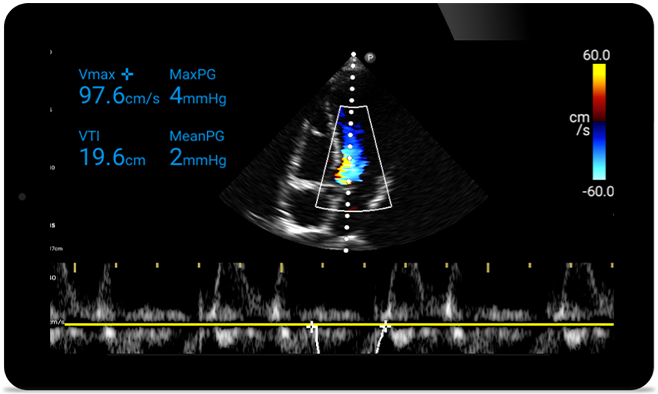

Jeśli w grę wchodzi serce, liczy się każda sekunda

Gdy liczy się dosłownie każda sekunda, przenośny ultrasonograf Lumify pozwala niezwłocznie wykonać obrazowanie w wysokiej rozdzielczości — gdziekolwiek jesteś.